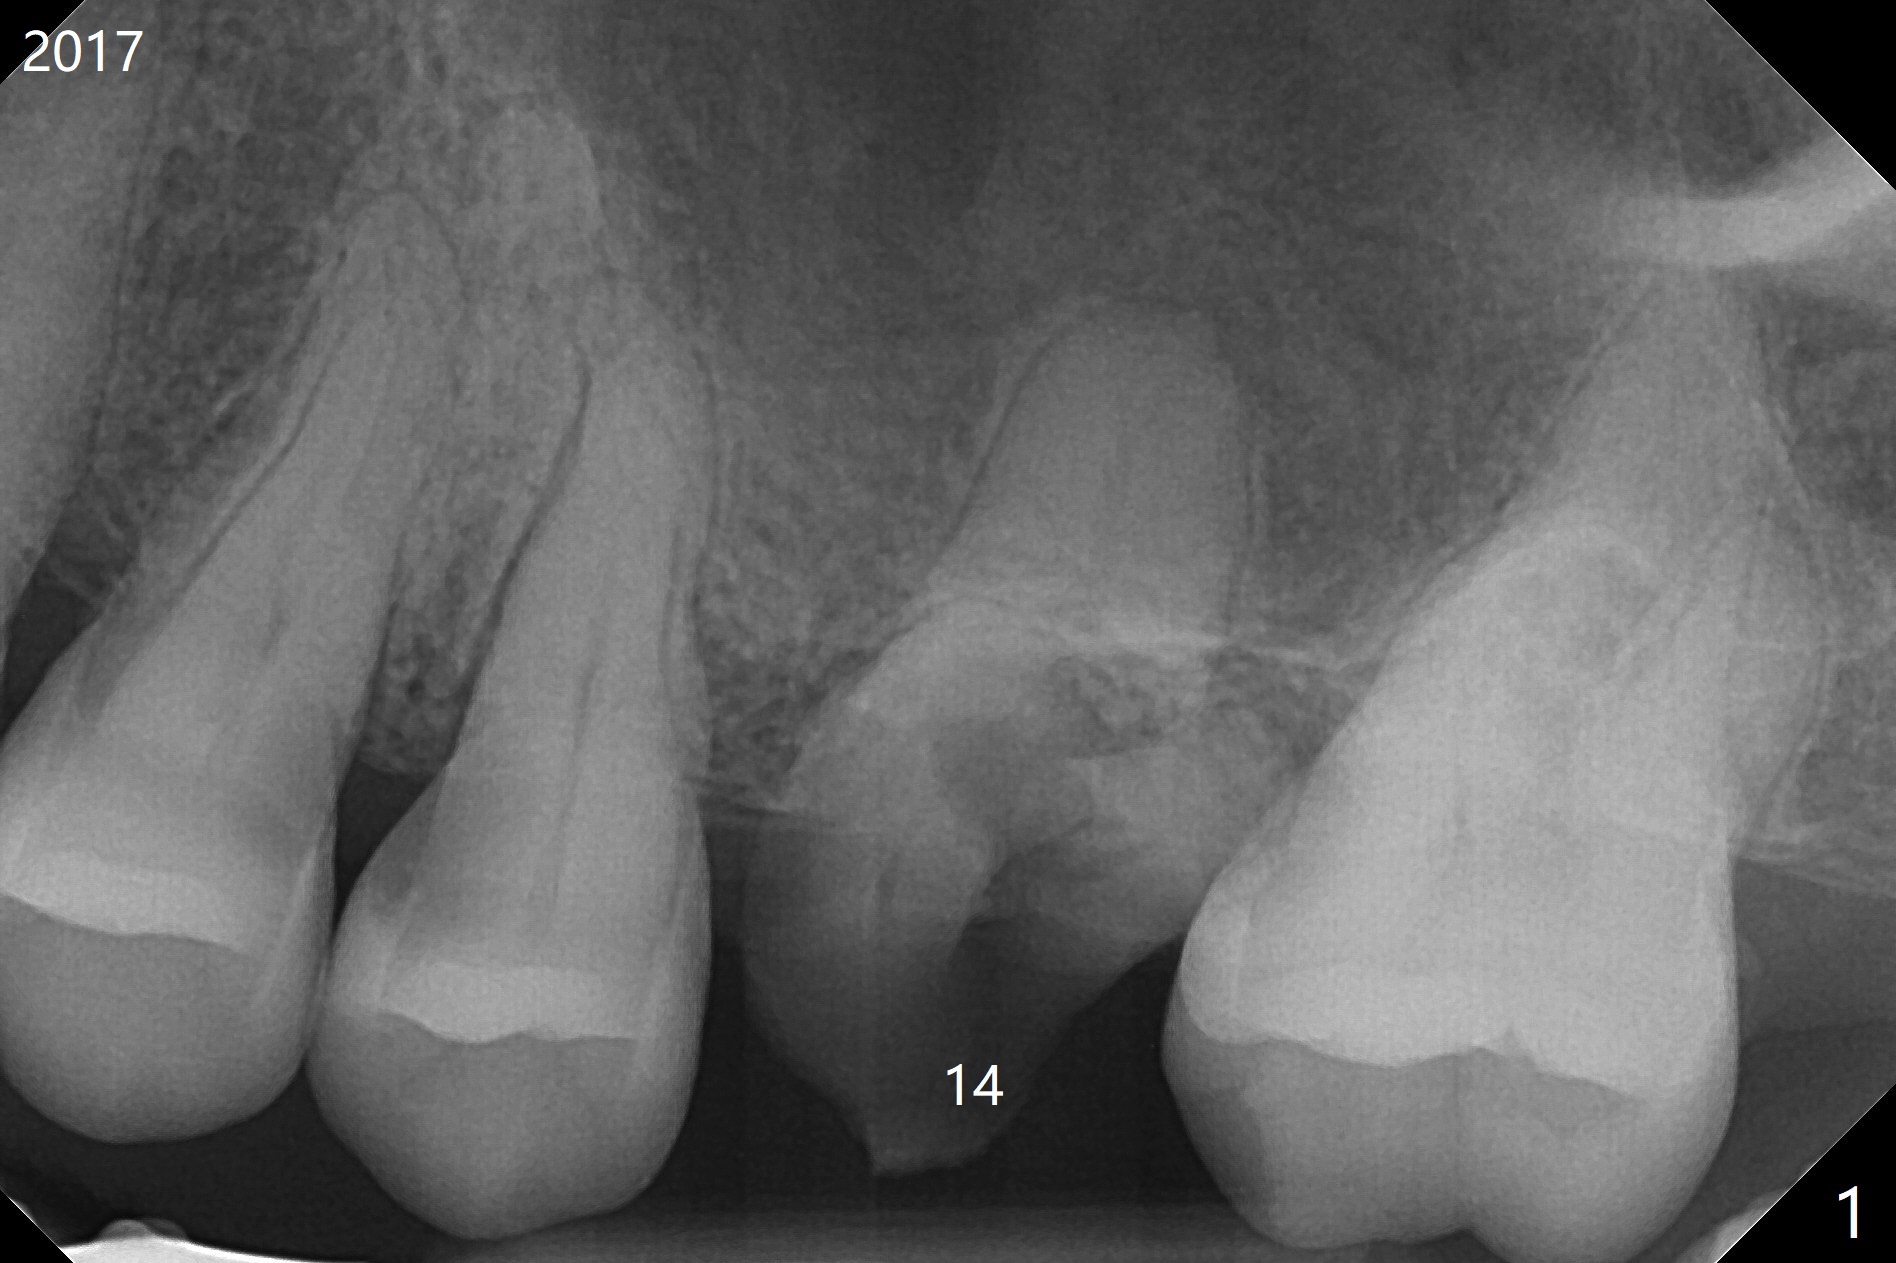

A 59-year-old nervous woman has poor dentition with upper left pain (Fig.1). Composite was placed at #12 and sedative filling at #13 two years ago. If the tooth #14 causes discomfort, it should be extracted for bone graft or immediate implant (Fig.4). PRF will be prepared (x2, white and red). The implant will be placed slightly palatal (P, Fig.2), since the residual buccal roots are more likely associated with buccal plate bone loss. If she agrees with treatment planning, take 5x5 cm CT for the bone loss and sinus. Sinus lift seems necessary because of short bone and septum (Fig.2,3).